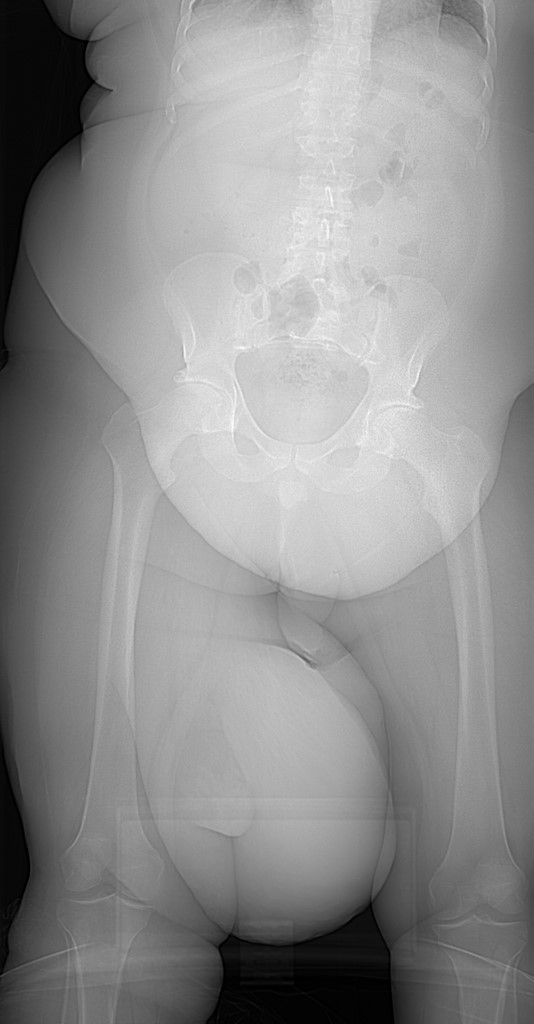

It's time for BIDMC Musculoskeletal Imaging & Intervention's interesting case of the week! ⬇️ ⬇️ ⬇️ Case # 122: History withheld. Diagnosis? Reply by Friday, March 31! #MSKRad #MedTwitter #RadRes #RadFellows

Case # 122:

History withheld.

Diagnosis?

Reply by Friday, March 31!

#MSKRad #MedTwitter #RadRes #RadFellows